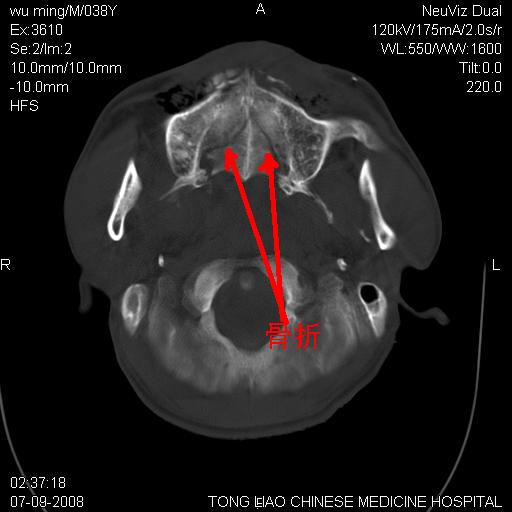

颅底多发骨折。

颅底多发骨折.

颅底多发骨折.上颌骨多发骨折

骨折

颅底多发骨折!支持!

多发性颅骨骨折